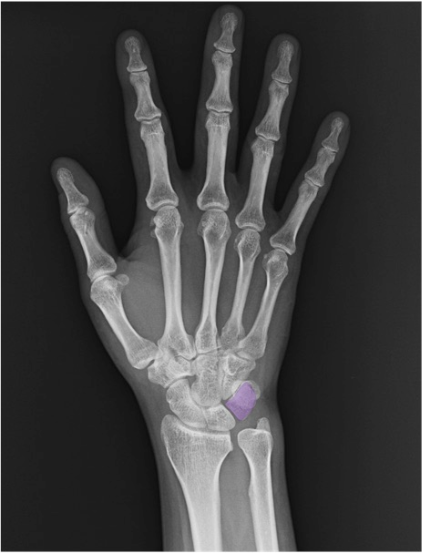

三角骨(triquetrum)

尺側近位列に位置。PA正面像では豆状骨(pisiform)に重なりやすいため輪郭が不明瞭なことがあります。斜位像では輪郭把握が容易。